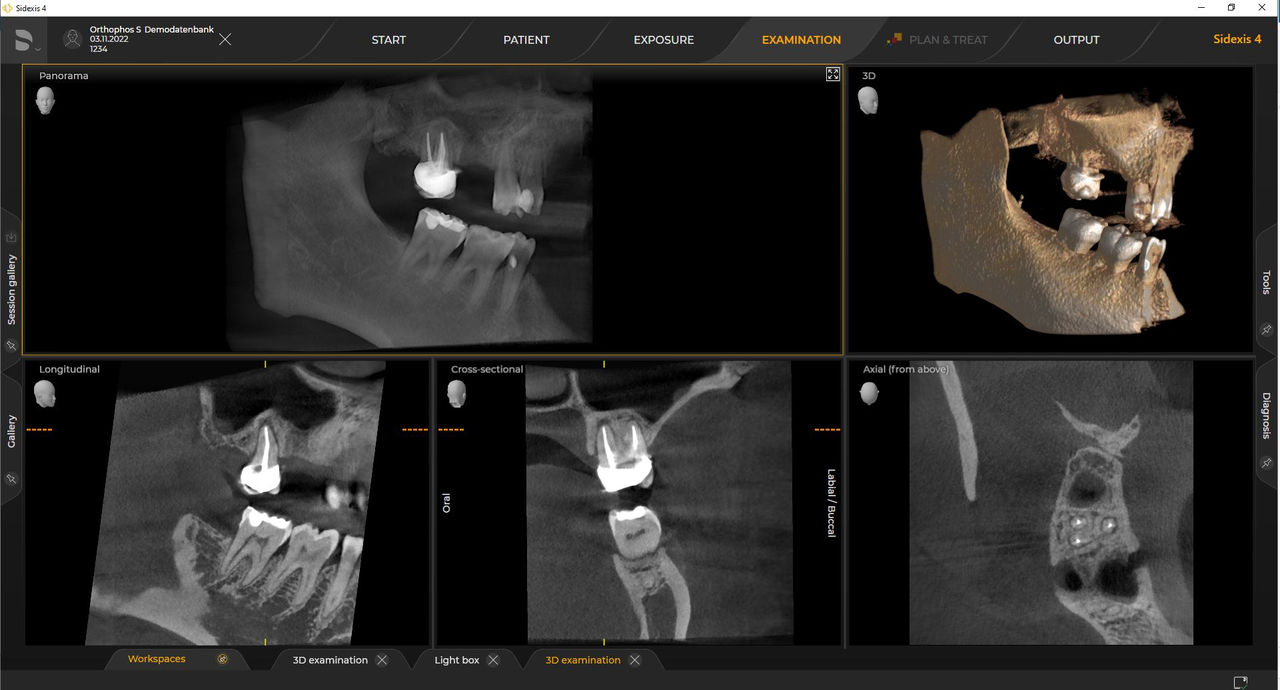

Las unidades de radiología de Dentsply Sirona funcionan exclusivamente con Sidexis 4. Sin embargo, la migración de datos de Sidexis XG a Sidexis 4 es muy fácil. Sidexis 4 permite una experiencia digital completa con las últimas herramientas